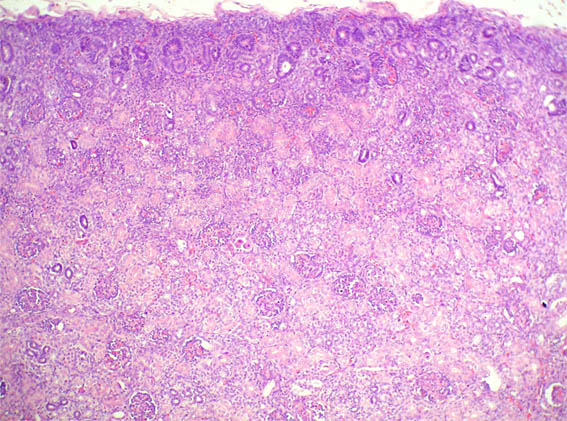

En ambos riñones fetales se observa lo mostrado en las siguientes imágenes.

Figura 1.

H&E, X100.